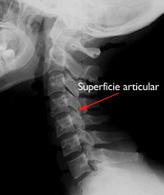

Superficie articular cervical

Inyección en superficie articular de la columna cervical